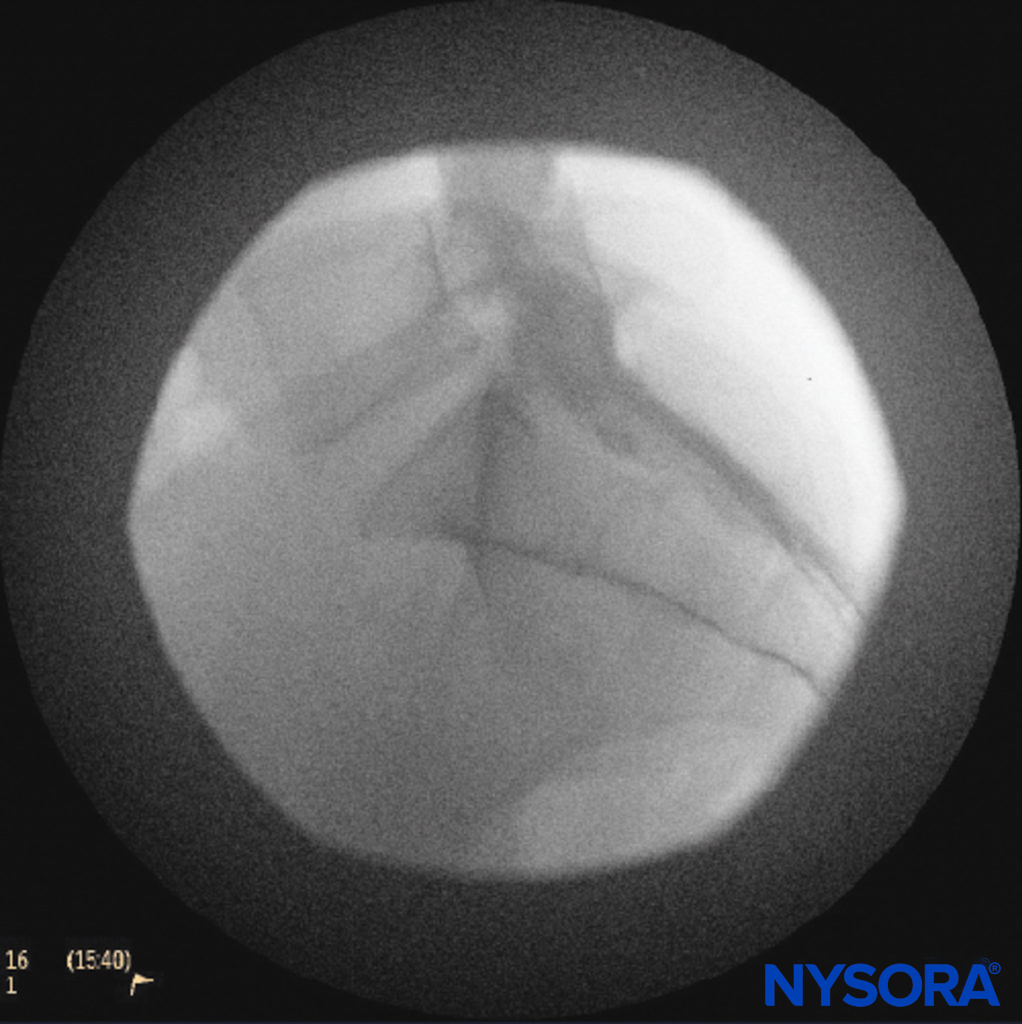

A small-gauge 1.5-inch needle is then utilized to infiltrate the skin over the sacral hiatus using 3-5 mL of 1%-1.5% plain lidocaine HCl (Figure 3). If fluoroscopy is utilized, a lateral view is obtained to demonstrate the anatomic boundaries of the sacral canal. We routinely leave the local anesthetic infiltration needle in situ for this view because it demonstrates whether the approach is at the appropriate level for subsequent advancement of the epidural needle. With fluoroscopy, the caudal canal appears as a translucent layer posterior to the sacral segments. The median sacral crest is visualized as an opaque line posterior to the caudal canal. The sacral hiatus is usually visualized as a translucent opening at the base of the caudal canal. The coccyx may be seen articulating with the inferior surface of the sacrum (Figure 4).

FIGURE 4. Lateral fluoroscopic image demonstrating the boundaries of the caudal canal.